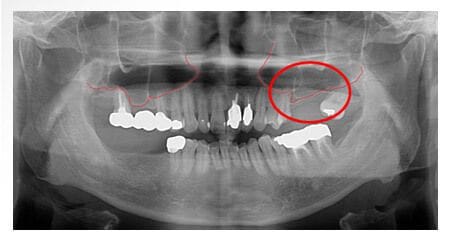

X 光片

術前

標記處骨頭高度不足